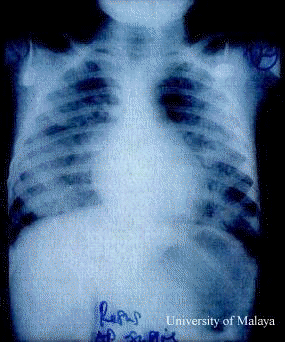

The association of pulmonary edema with CNS disease without underlying cardiopulmonary disease is known as neurogenic pulmonary edema (NPE). NPE is characterized clinically by an often fulminant course marked by pulmonary vascular congestion, protein rich edema fluid and intra-alveolar hemorrhage.

Bakers description is particularly interesting because EV71 and polioviruses are enteroviruses. In his study of NPE following poliomyelitis, Baker noted that only patients with pathologic changes in the region of the dorsal nucleus of the vagus and the medial reticular nuclei of the medulla developed NPE. The pathogenesis of NPE is not so well defined but the physiologic changes have been described. Following an insult to the brainstem, there appears to be an overwhelming outpouring of catecholamines, esp noradrenalin. This produces peripheral vasoconstriction followed by systemic hypertension and a shift of blood from the high resistance systemic circulation to the relatively low resistance pulmonary circulation. This elevation in hydrostatic pressure damages the pulmonary capillaries with subsequent pulmonary hemorrhages. Experimental data also point towards an increase in pulmonary capillary permeability; thus the protein rich edema fluid. It is also shown in clinical studies that the heart suffers a severe knock : myocardial necrosis and echocardiographic evidence of severe cardiac dysfunction. It is the latter that might be misinterpreted as myocarditis. It has been argued that this may represent centrally mediated cardiac failure secondary to severe increase in left ventricular afterload.